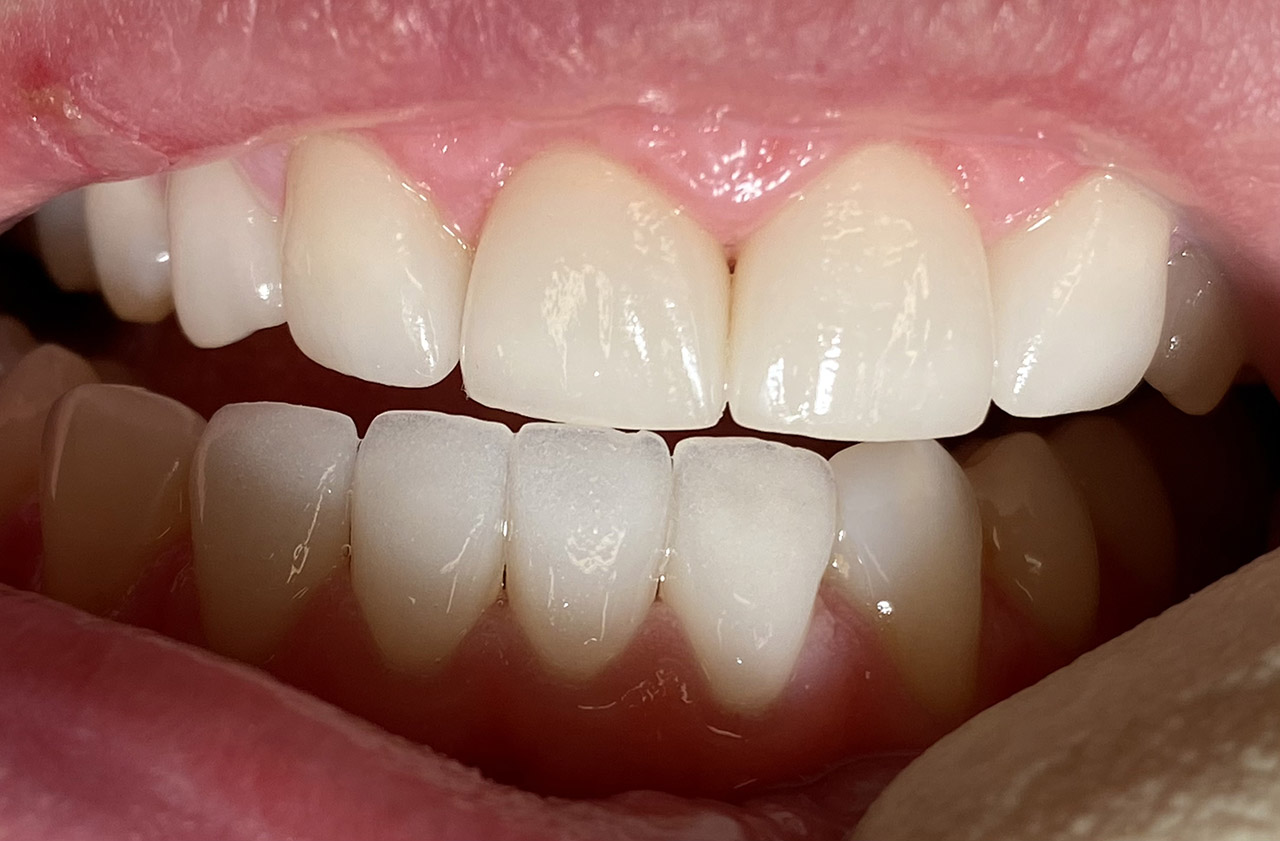

Ästhetische Zahnheilkunde / der komplexe Fall

Aplasien/Nichtanlagen, dadurch bleibende Milchzähne, Diasteme/Zahnlücken,

Bleaching/Bleichen, Positionierung der Zähne/Kieferorthopädie (Dr. Maija Eltz), Verblendung mit Veneers/Keramikschalen.

Vorher Nachher